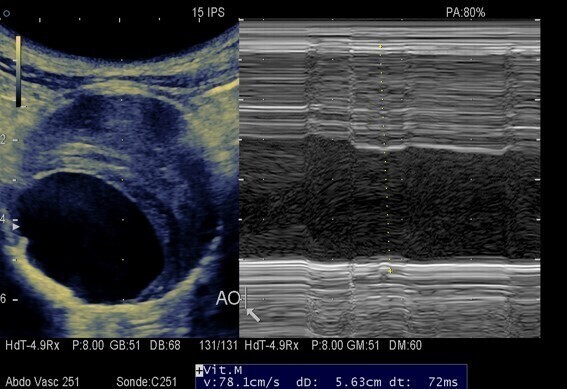

Cas clinique ; femme de 78 ans, tabagique 30 paquets-année, HTA, BMI à 35, consulte dans le cadre de ses RDFCV. Dépistage systématique de l'AAA, découverte fortuite de cet anévrisme (DAP 56,3 mm) , traité par endoprothèse, suites simples. Ses enfants ont été dépistés, 2 garçons et une fille, RAS.